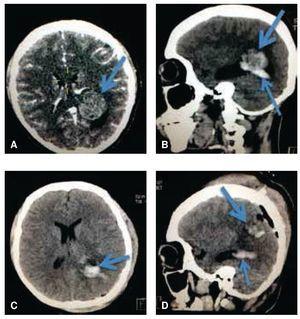

Se decide realizar resección de la lesión a través de un abordaje transulcar parietal izquierdo en el giro supramarginal, llegando al atrio del ventrículo lateral izquierdo, se identificó una lesión firme, violácea, de aproximadamente 3 x 3 cm de bordes regulares, multilobulada, se identificó un pedículo el cual se coaguló con bipolar y se extrajo la lesión en pieza única, enviándose a Patología, donde se reporta macroscópicamente un nódulo de 4.6 x 3.8 cm con superficie externa de aspecto fibroso, de color café grisáceo; al corte se observan bandas de fibrosis que rodean tejido color café rojizo de consistencia blanda. En el examen microscópico corresponde a una malformación vascular, compuesta por vasos sanguíneos de distintos calibres y con espesor aumentado debido al depósito de colágeno tipo I (colágeno maduro) que se hace más evidente con la tinción especial de tricrómico de Masson; se realizó la tinción de fibras elásticas (tinción de Verhöeff) en el que se hace evidente la presencia de la capa elástica en los elementos arteriales de la lesión. El diagnóstico definitivo histopatológico es de MAV (figs. 2, 3 y 4).

Figura 3. A) El aspecto histológico de la malformación vascular está compuesto por luces vasculares dilatadas de distintos calibres, con paredes engrosadas y colagenizadas demostradas por el color azul (flecha) en la tinción de tricrómico de Masson. B) En la pared de algunos vasos sanguíneos se identifican fibras elásticas, que se denotan por el color negro (flecha) con la tinción argéntica de Verhöeff.